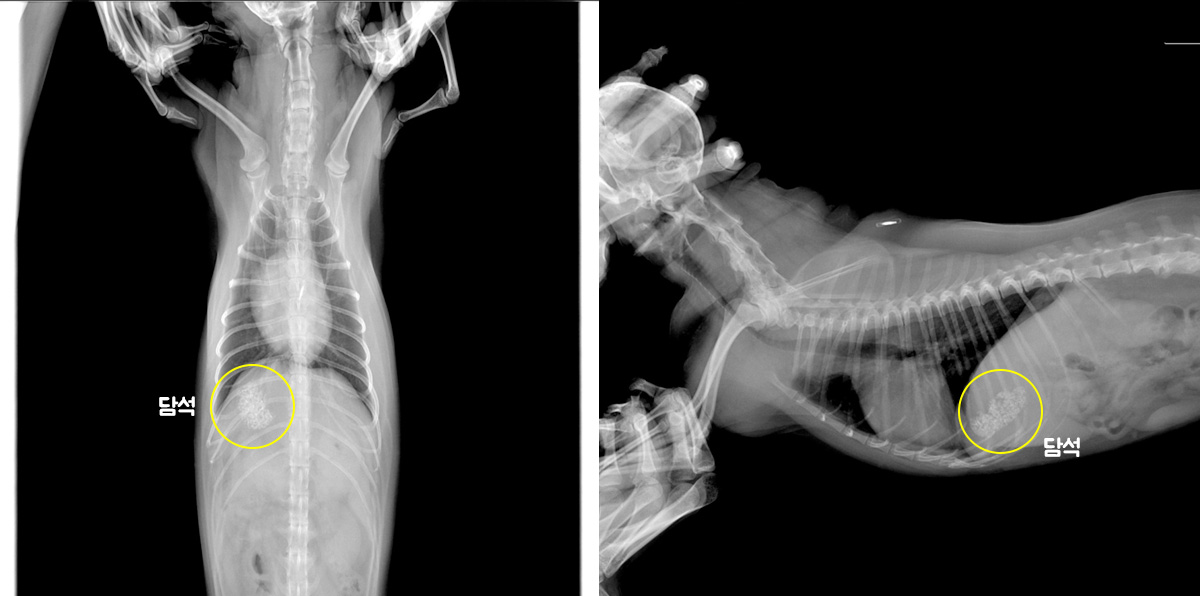

철원동물병원 강아지 비장종양 조기발견이 중요한 이유는? : 네이버 블로그

7살 강아지 비장종양(비장암)수술 치료 후기/안산동물병원 : 네이버 블로그